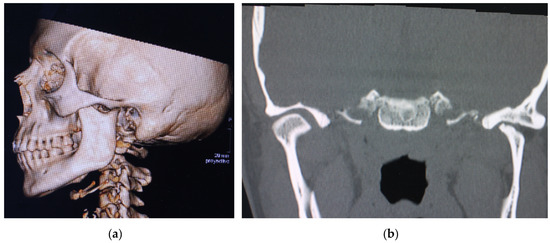

Case Presentation